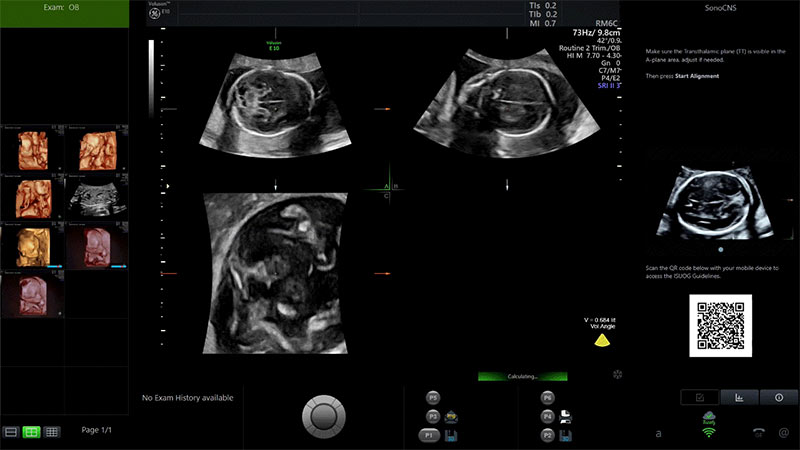

I casi d’uso sono i più svariati. Dall’elaborazione delle immagini con algoritmi intelligenti e consapevoli del contesto al settore sanitario: ad esempio, i dispositivi a ultrasuoni Voluson di GE Healthcare, informa Microsoft, sfruttano reti neurali pre-addestrate che aiutano l’ecografista che utilizza la sonda a segmentare automaticamente specifici piani di imaging da un volume e a eseguire misurazioni manuali. Con funzionalità basate su Windows ML e DirectML.